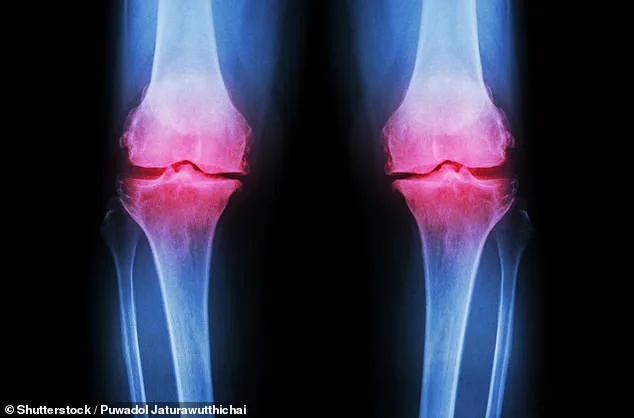

Osteoarthritis, which impacts over 10 million people nationwide, occurs when cartilage breaks down, leading to chronic joint pain and stiffness. Current treatments often rely on pharmaceuticals with side effects or physiotherapy that many struggle to maintain. Now researchers at the University of Nottingham propose a low-cost alternative: inulin, a prebiotic fibre found naturally in chicory root and artichokes.